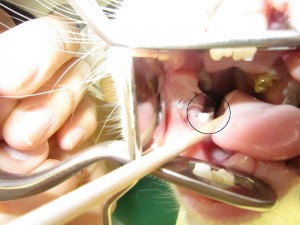

処置前 (2)

上顎の臼歯です。

外側に伸びており、頬にささっています。